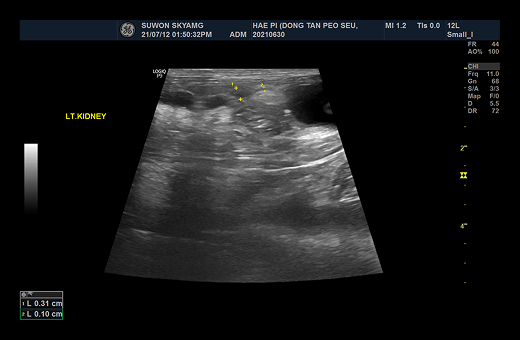

1-1 1-2

요관 확장으로 인해 SUB 수술적 치료 진행

요관 폐색의 진단에 있어서 가장 중요한 검사는 방사선, 초음파, CT 검사 등의 영상 진단입니다.

· 초음파 검사

초음파 검사를 통해서 요관의 확장 정도와, 결석의 위치 등에 대한 정보를 확인하게 되며, 이로 인한 폐색에 따른 신우 확장 정도를 평가하게 됩니다. 신우 확장이 명확하고, 결석의 위치 정보 등이 확인되면, 수술적인 치료를 통한 폐색의 해소를 목표하게 됩니다.